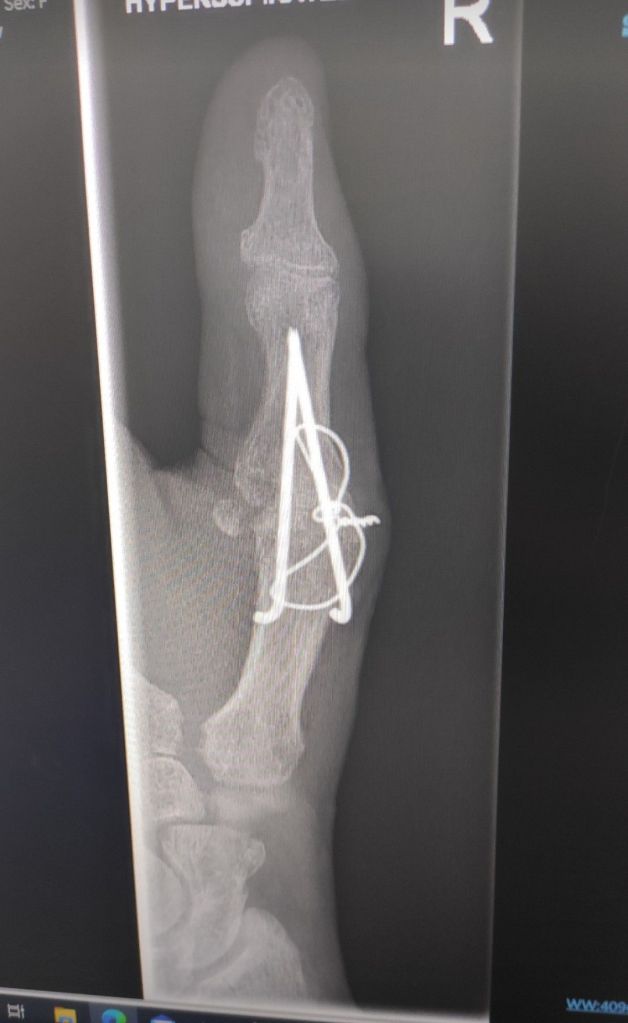

Now the swelling is massively reduced I (think I) can feel the tip of a pin that’s fusing the MCP joint, so I believe it is this that stops me from flexing the top of the thumb fully. (But I could be delulu) And also the weird shooting pains I get in the forearm. I’d love to know what this is, maybe a bit of nerve compressing?

My grip strength is back to before surgery, which is great, dexterity is really good. The book nook I’ve been making for 2 months really helped in that department. It’s now getting the wrist in check and strengthened

Available here a video of mt hand flat on the floor. This is 160 days post op.